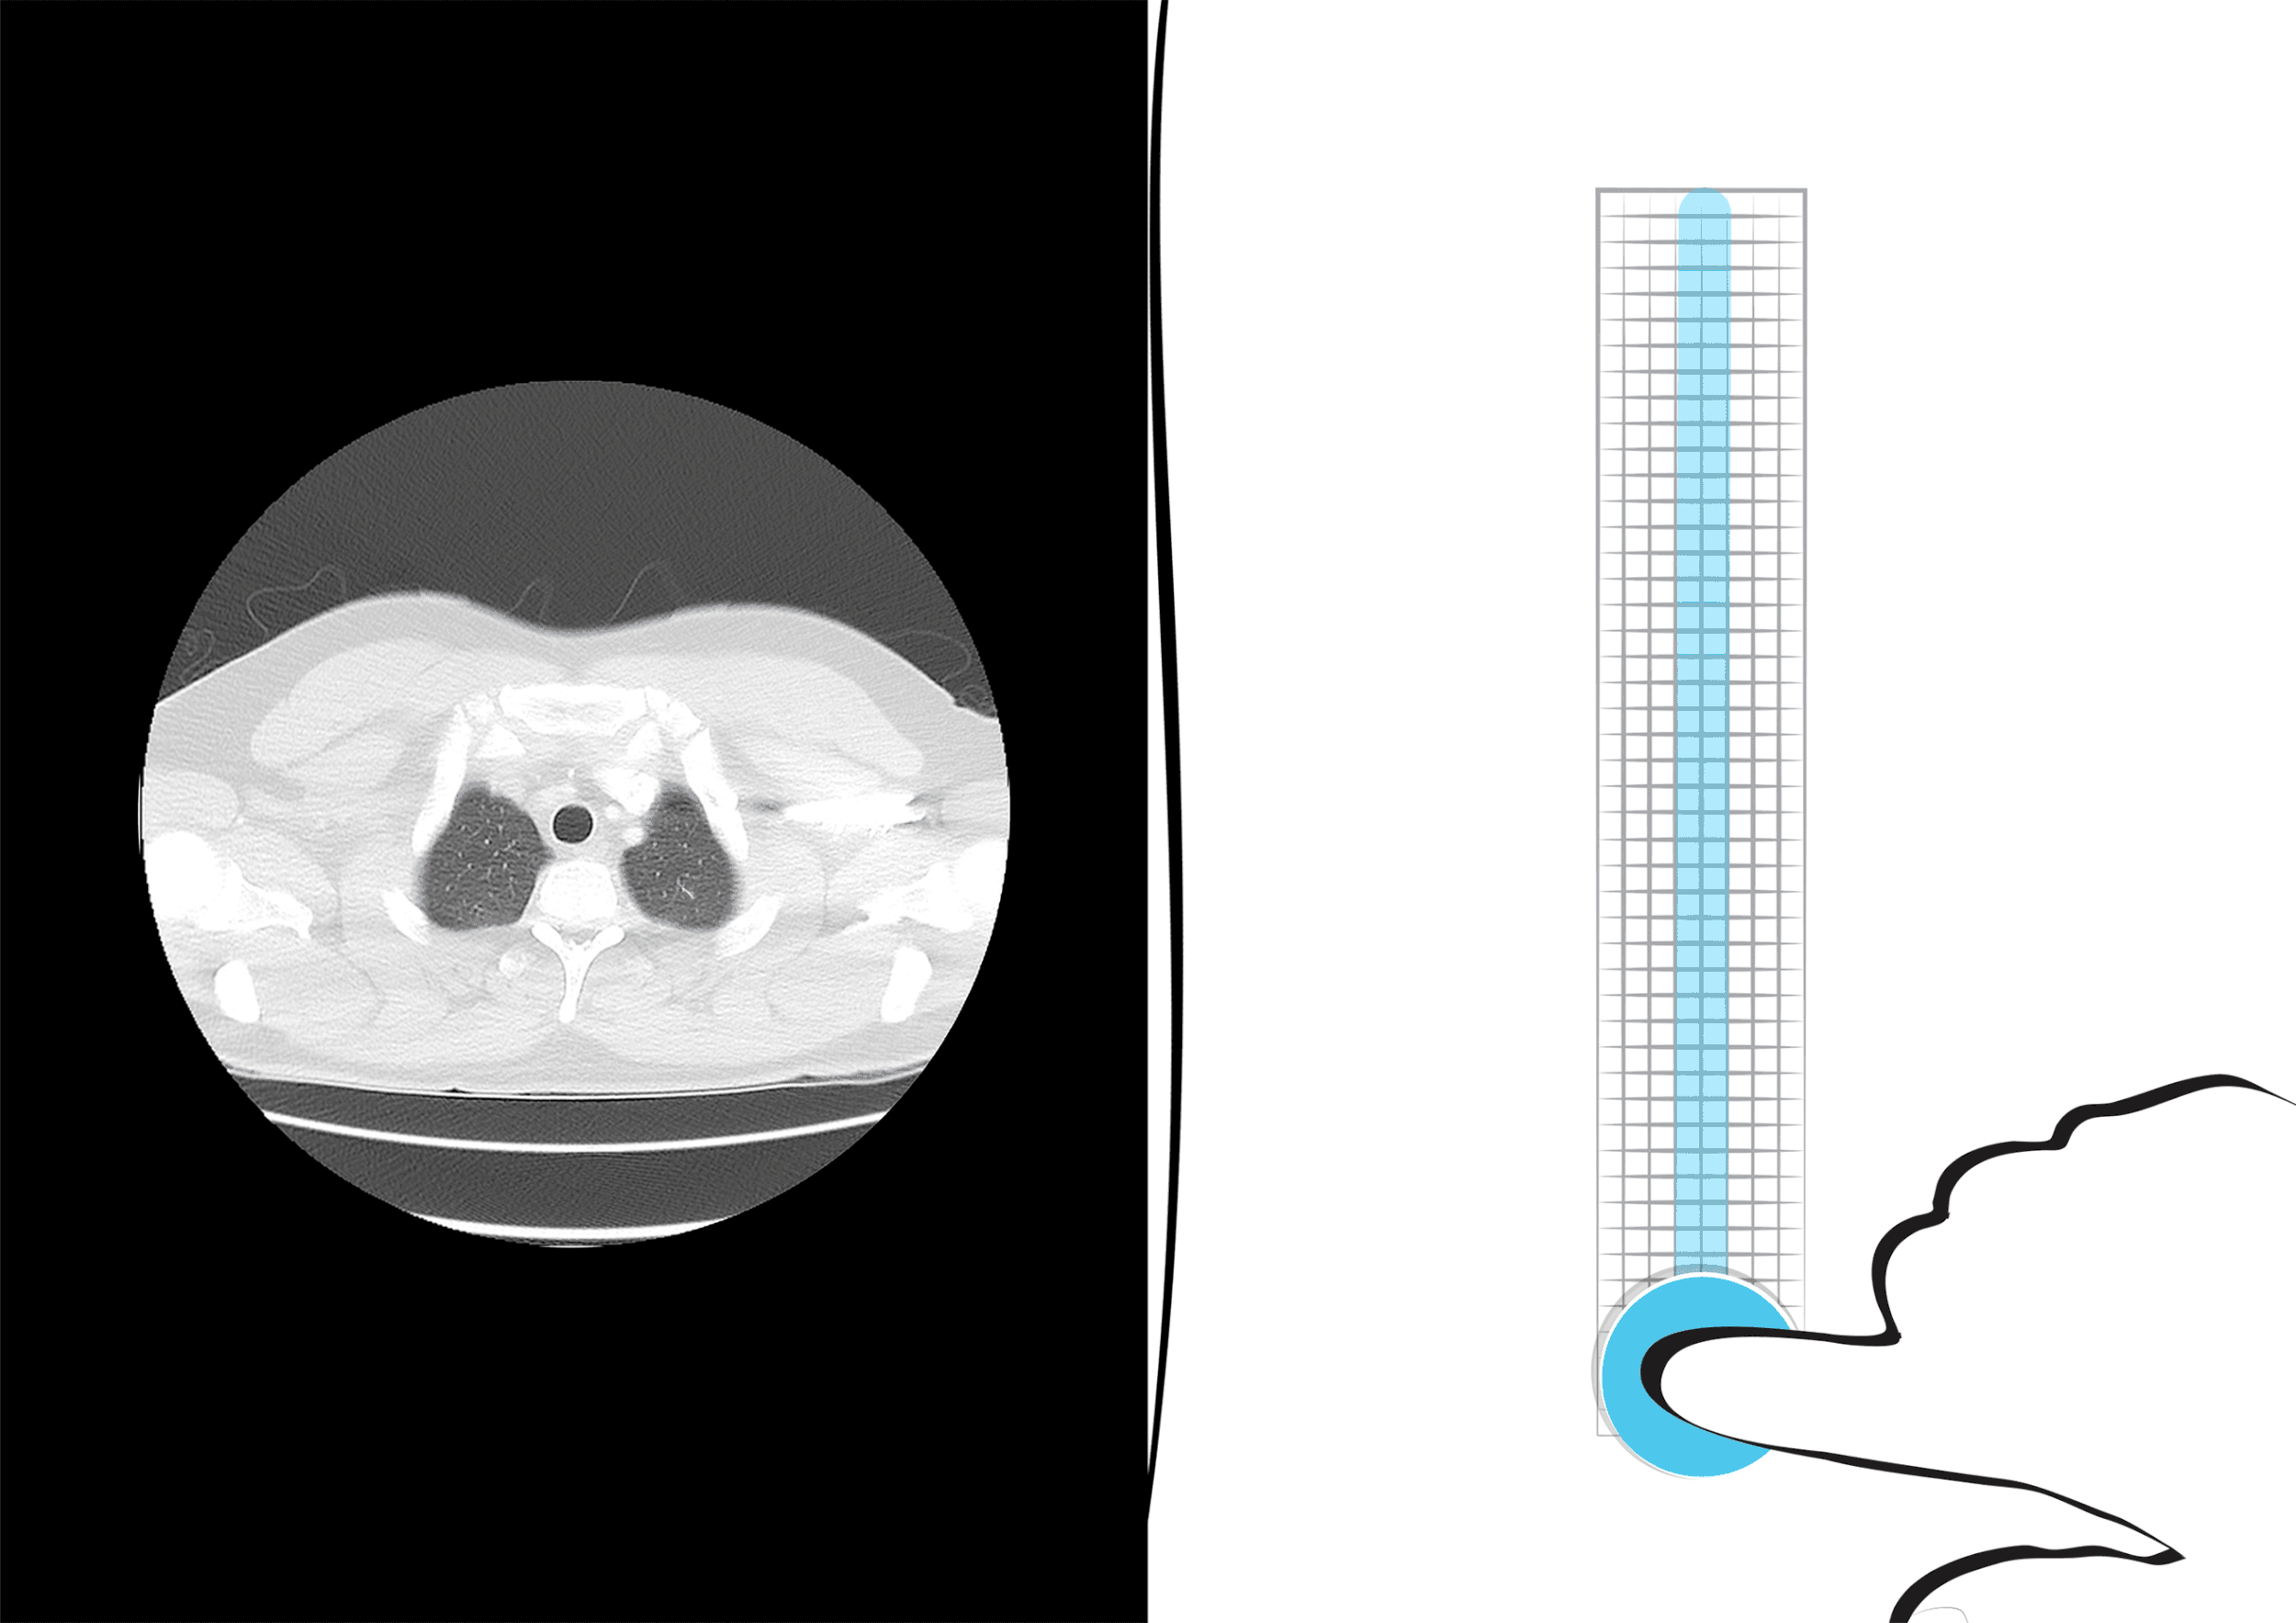

Implementing the Jacquard by Google technology in a medical setting advances patient care by making the doctor’s interaction with the patient natural seamless, and most of all efficient. It's purpose can be functional like navigating through imaging slices during surgery guiding the surgeon through the patient’s anatomy while preserving the sterile environment or recreational to serve as distraction for the patient during a physical.